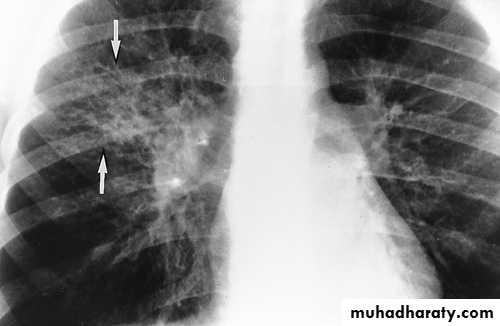

CXR: interstitial or bronchopneumonic, involve mainly the lower lobes. Bilateral diffuse infiltrates, lobar pneumonia or hilar lymphadenopathy can occur in up to 30% . Pleural effusions may occur.

Hilar involvement